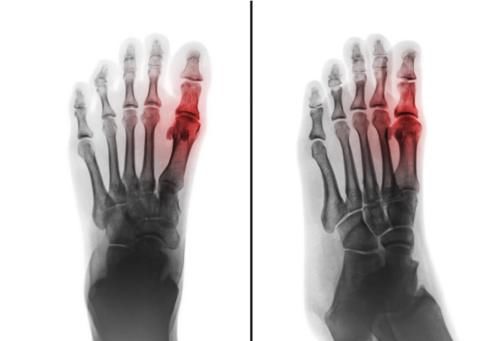

那么究竟怎么样才算“痛风”呢?很简单,你得确实是因为尿酸高引起了尿酸盐沉积在关节里,引起关节确实的肿痛不适,才算。

是的,所谓“痛风”,是一种尿酸盐沉积关节导致关节发炎从而红肿热痛的疾病。你可以简单理解为:“痛风”=“尿酸高”+“关节疼”。